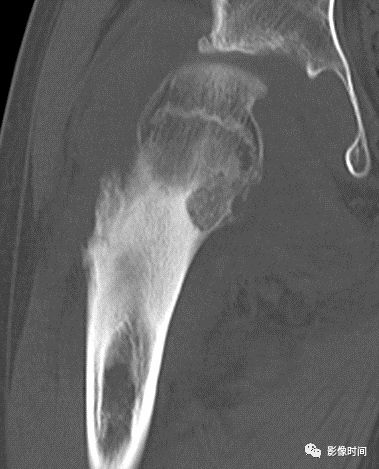

(二)膨胀性破坏  膨胀性破坏是地图样破坏的特殊形式,影像学表现为骨质破坏区骨膨胀,周围可见不同程度扩张的骨壳(图 5、图 6、图 7、图 8)。

膨胀性破坏是由于肿瘤从骨皮质内面破坏,骨外膜增生形成新生骨造成膨胀的。

引起膨胀性破坏见于大多数良性肿瘤和肿瘤样病变如单纯性骨囊肿,动脉瘤样骨囊肿、内生软骨瘤和软骨粘液纤维瘤等,少数也可见于恶性肿瘤如转移瘤、骨髓瘤等。

图 5  膨胀性破坏:动脉瘤样骨囊肿